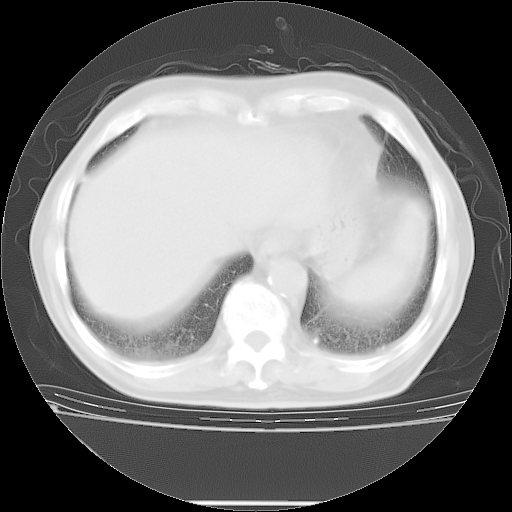

胸腹部CT,诊断意见:左上肺叶钙化灶、左侧胸膜局限性增厚并钙化、胆囊炎。描述部分肺组织呈磨玻璃样改变。

今天复查肺部CT,发现双肺广泛磨玻璃样改变。所以我把3月19日和5月9日相隔50天的肺部CT上传。请大家会诊。

5月9日肺部CT(在4月27日齐鲁医院肺部CT描述部分肺组织磨玻璃样改变,12天后肺组织广泛磨玻璃样改变)

2009年5月9日肺部CT

大致读了系列胸部CT:纵隔窗无明显异常,肺窗:从4、27至今:主要是双肺中下野外带可见毛玻璃样改变,目前处于急性肺泡炎阶段,至于原因考虑1、结替组织或胶原血管性疾病所致?2、恶性疾病如恶组在肺部所致的表现或细支气管肺泡癌?3、药物或其它原因如肺蛋白沉着症所致肺泡炎目前不太可能?总之,明天就去请我院的呼吸科、感染科、血液科和临免专家会诊哈。